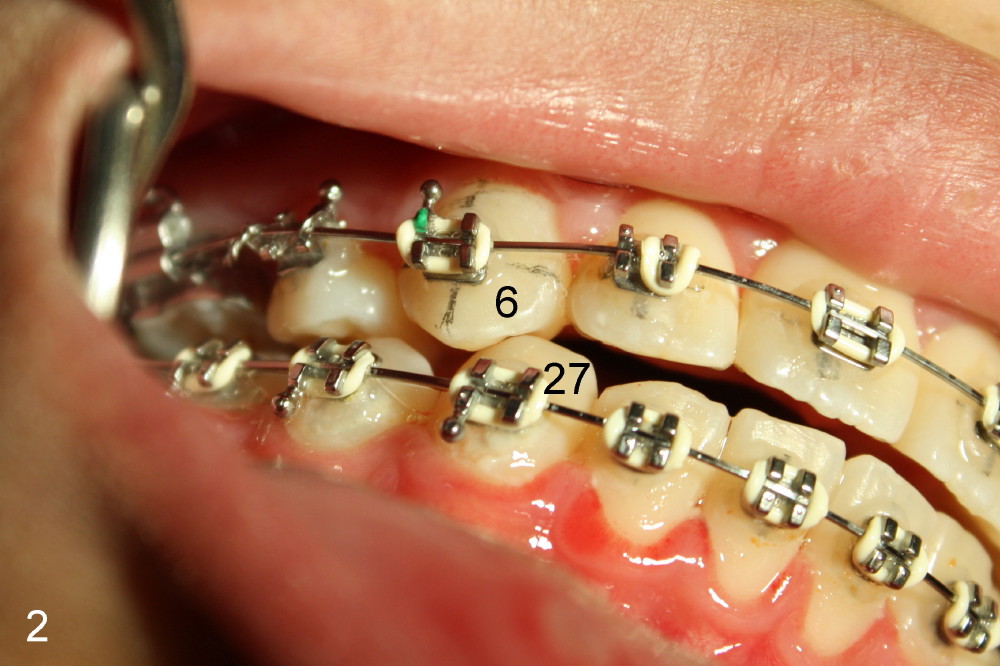

Christina has had the most complicated orthodontic treatment: phase one, mini-implant, extraction, and distalization. When canine Class I occlusion is achieved, anterior open bite is noted (Fig.1 between arrowheads). It is probably due to premature contact between the right upper and lower canines (Fig.2: #6, 27).